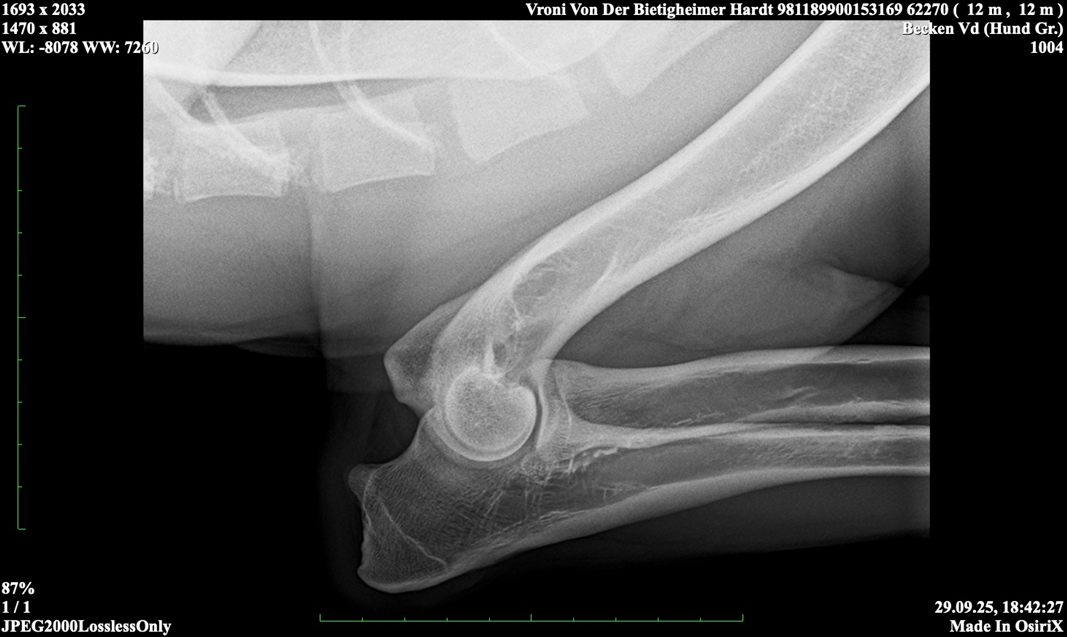

Vroni von der Bietigheimer Hardt

SZ. 2395403; WT: 27.09.2024;

HD ZW: kW25/02 „69“ Größen-ZW: kW25/02 „101!